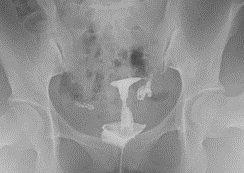

子宮卵管造影(HSG:HysteroSalpingoGraphy)

外陰部より造影剤を子宮の中に注入して子宮内腔の状態と卵管の通過性を調べる検査です。

子宮卵管造影